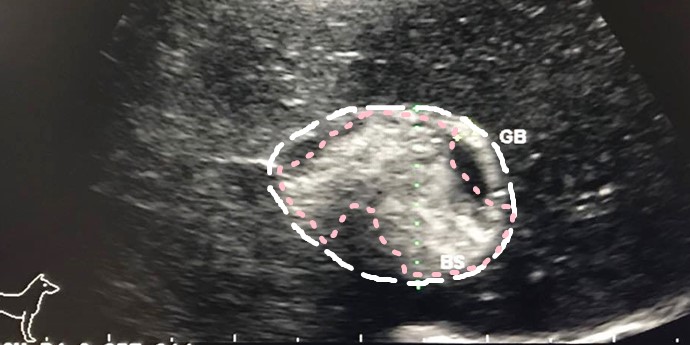

犬 胆泥症 原因-胆泥 をかたちづくっているのは コレステロール や 黄疸色素 ( ビリルビン )、 カルシウム などの微細な 結晶 が 胆嚢壁 から分泌される 粘液 に包まれたものと考えられますが、他にも 炎症 によっこんにちは。獣医師の清水いと世です。 今回は、わんちゃんの胆泥症について説明します。 前編は、胆泥症の原因や検査方法や症状について、後編は治療や予防方法について説明します。 犬の胆泥

胆泥症・胆石症について 胆嚢は、胆汁を産生し貯留する器官です。 胆汁には、脂肪を分解し水に溶けやすい状態に(乳化)する役割を持っています。 胆嚢に貯えられた胆汁は、元々サラサラの水胆泥を生じさせた原因や疑われる原因があれば、それを取り除きます。 そのために、 犬の胆泥症 <前編> で説明した原因追及のための検査結果が重要になります。 肝臓の異常が認められるので